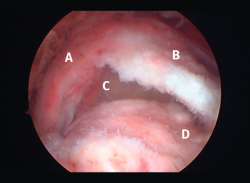

Figura 2. Rotura del manguito rotador en forma de U. A: tendón infraespinoso; B: tendón supraespinoso; C: cabeza humeral.

Figura 5. Rotura de tipo C1. A: rotura pequeña de espesor completo del supraespinoso; B: cabeza humeral.

Sin embargo, las clasificaciones basadas en el tamaño de la rotura deben ser bidimensionales, ya que la visión unidimensional puede ser engañosa, al mostrar el tamaño de la rotura solo desde el plano anteroposterior(4). Por esta razón, proponemos el sistema de clasificación del manguito posterosuperior sugerida por Snyder, que aporta información no solo del tamaño, sino del número de tendones afectados y la presencia de tejido cicatricial(7). En las lesiones de tipo C1 la lesión atraviesa todo el espesor del tendón y en el eje transversal es pequeña y punzante (Figura 5). Las de tipo C2 son roturas de espesor completo pero la distancia entre los extremos de la rotura es menor de 2 cm con escasa retracción (Figura 6). En las de tipo C3 la rotura afecta en sentido transversal entre 3 y 4 cm con mayor retracción implicando 2 tendones (Figura 7). Y las de tipo C4 son la rotura masiva del manguito de los rotadores con una afectación de espesor completo de toda la anchura de 2 o más tendones asociando importante retracción (Figura 8).